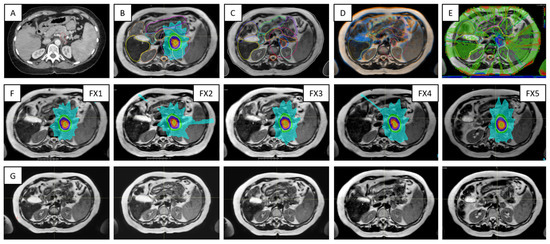

Figure 9 outlines key processes and various types of data required for the Unity treatments in the case of a pancreas patient. For each ATS data set acquired for planning, there was at least one verification scan acquired prior the treatment delivery and one other scan collected during beam on. The first verification scan was used to confirm stability of the patient setup and adequate representation of the ATS plan at the time of delivery, while the beam on time scan was used for research activities related to dose-of-the-day and dose accumulation.

Figure 9. Highlights of the online adaptive workflow for a pancreas case —i.e., Patient 10 in Table 1: (A) CT image required for the assignation of bulk electron density values to contours on MR image data; (B) MR-based reference plan; (C) contours defined during the first treatment fraction; (D) image registration between MR images acquired for planning and verification for Fraction 1; (E) dose difference map representative for the secondary MU calculations; (F) the row shows the ATS plan for each of the five treatment fractions; (G) verification images corresponding to data from (F).